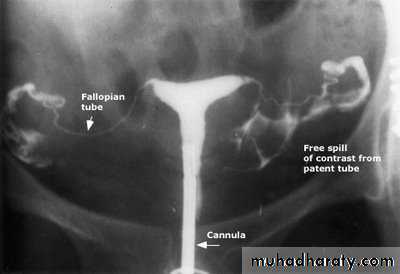

Hysterosalpingography

Indication to confirm the patency of uterine tube.Complication spread of the infection (so give antibiotics before doing Hysterosalpingography)

Causes of tubal blockage infection (chlamydia), trauma, surgery, congenital